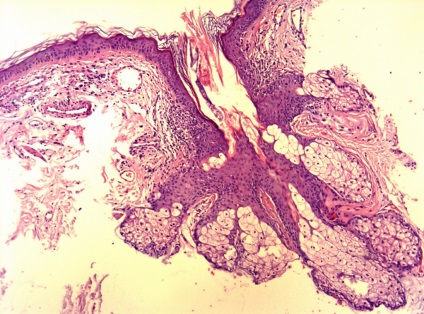

Ma már többféle bőr biopszia, köztük - tűbiopszia, excisional biopszia és derma biopszia. Dermatomális és excíziós bőr-biopszia végre az „akut” vagy „nyitott” módon. Amikor egy szikével biopszia dermatomális felületi réteg a bőr, míg a excisional biopszia - kivágtuk nagyobb bőrterületet, majd varrókészülék (fénykép 1). Ugyanezt a technikát használunk, és ha a biopszia musculocutaneous csapóajtót, ha egyidejűleg kimetszett bőr, a bőr alatti szövet és izom lebeny alá.

Ábra. 4 Skin tumorképződés - jelzi excisiós biopszia

Következtetés (patológus MD Karev VE): egy jóindulatú daganat tömegének faggyúmirigy; haemangiomatosis bőrben, cutan vasculitis (gyulladásos elváltozások érfalak).